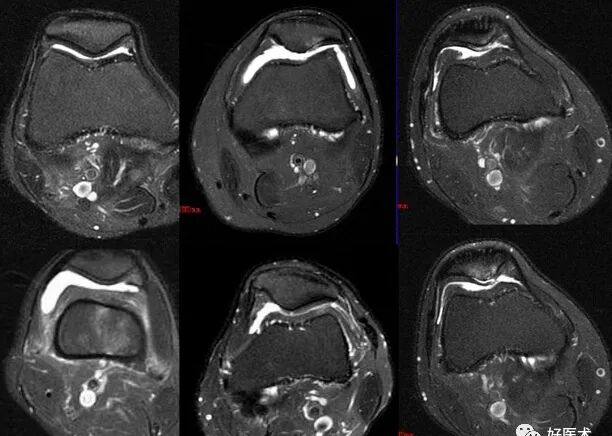

• MRI检查:对髌骨软化症有较大的诊断价值,能够很好的显示关节积液、软骨退变及软骨下骨的囊性变等表现。

MR|判断髌骨软骨软化是以软骨内信号改变和软骨表面形态来诊断。病变可使髌骨软骨轮廓不同程度发生改变,表面毛糙,内部信号异常。

MRI表现局灶性低信号,T1T2加权像轻度轮廓改变,厚度变薄,软骨下有硬化的囊变

髌骨软骨软化症MRI表现:

0级:

A:SE序列T1加权像

B:SE序列T2加权像

C:STIR像

D:PGE序列T1加权像

Ⅰ级:

Ⅱ级:

Ⅲ级:

Ⅳ级: